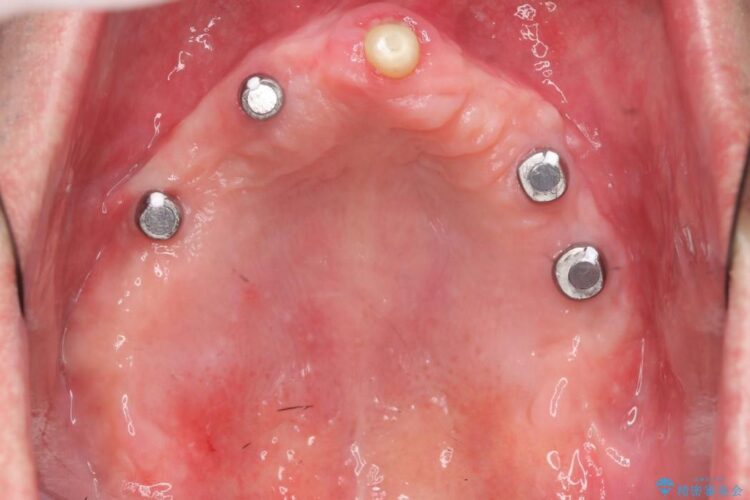

本症例では失った歯を補うため、マグネットを使用したインプラントの入れ歯(マグネットオーバーデンチャー)という維持機構を使用しました。

マグネットタイプは無理な側方力がかかると入れ歯が外れるため、口腔内に設置する装置が他の維持装置と比べてインプラント体や支台歯へ大きな負担がかかることを防止してくれます。

また着脱が簡単であり、磁石の固定によりガタつかず非常に安定します。